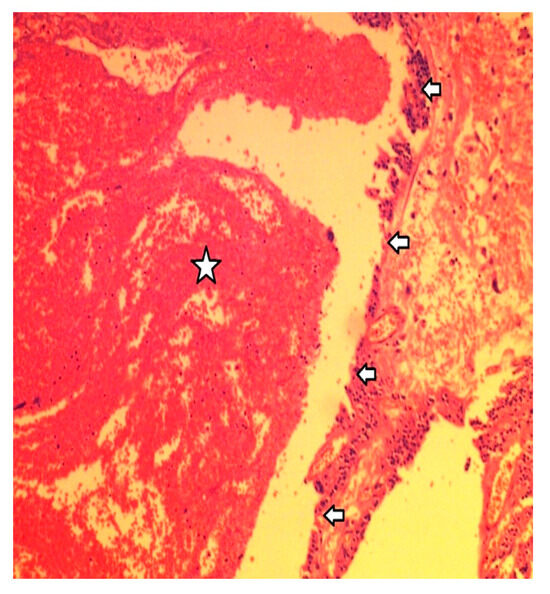

2.4. Histology